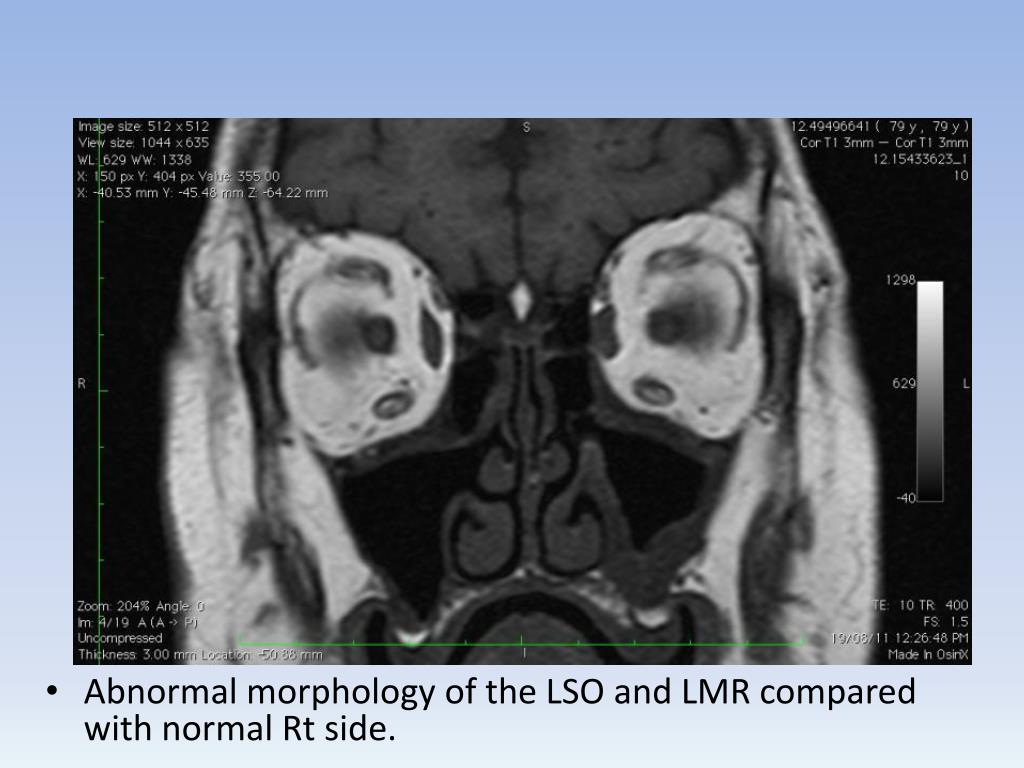

11. Abnormal morphology of the LSO and LMR compared with normal Rt side.

12. No intervening fat between LMR and orbital wall, nor between L SO and MR (compared to the Rt).